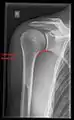

X-ray

Projectional radiography views of the shoulder include:

- AP-projection 40° posterior oblique after Grashey

The body has to be rotated about 30 to 45 degrees towards the shoulder to be imaged, and the standing or sitting patient lets the arm hang. This method reveals the joint gap and the vertical alignment towards the socket.[24]

- Transaxillary projection

The arm should be abducted 80 to 100 degrees. This method reveals:[24]

- The horizontal alignment of the humerus head in respect to the socket and the lateral clavicle in respect to the acromion

- Lesions of the anterior and posterior socket border, or of the tuberculum minus

- The eventual non-closure of the acromial apophysis

- The coraco-humeral interval

- Y-projection

The lateral contour of the shoulder should be positioned in front of the film in a way that the longitudinal axis of the scapula continues parallel to the path of the rays. This method reveals:[24]

- The horizontal centralization of the humerus head and socket

- The osseous margins of the coraco-acromial arch and hence the supraspinatus outlet canal

- The shape of the acromion

This projection has a low tolerance for errors and, accordingly, needs proper execution.[24] The Y-projection can be traced back to Wijnblath’s 1933 published cavitas-en-face projection.[25]

CR. shoulay film.

Transaxillary conventional radiography

Y-projection conventional radiography